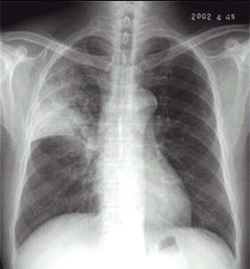

02卷-5.女性,55岁,胸闷、气短5天,加重1天。诊断(本题满分2.00分)

左侧胸腔积液

A.右上肺炎

B.左侧胸腔积液

C.左下肺不张

D.左肺癌

本题答案:B

题目解析:【该题针对“X线-胸腔积液”知识点进行考核】